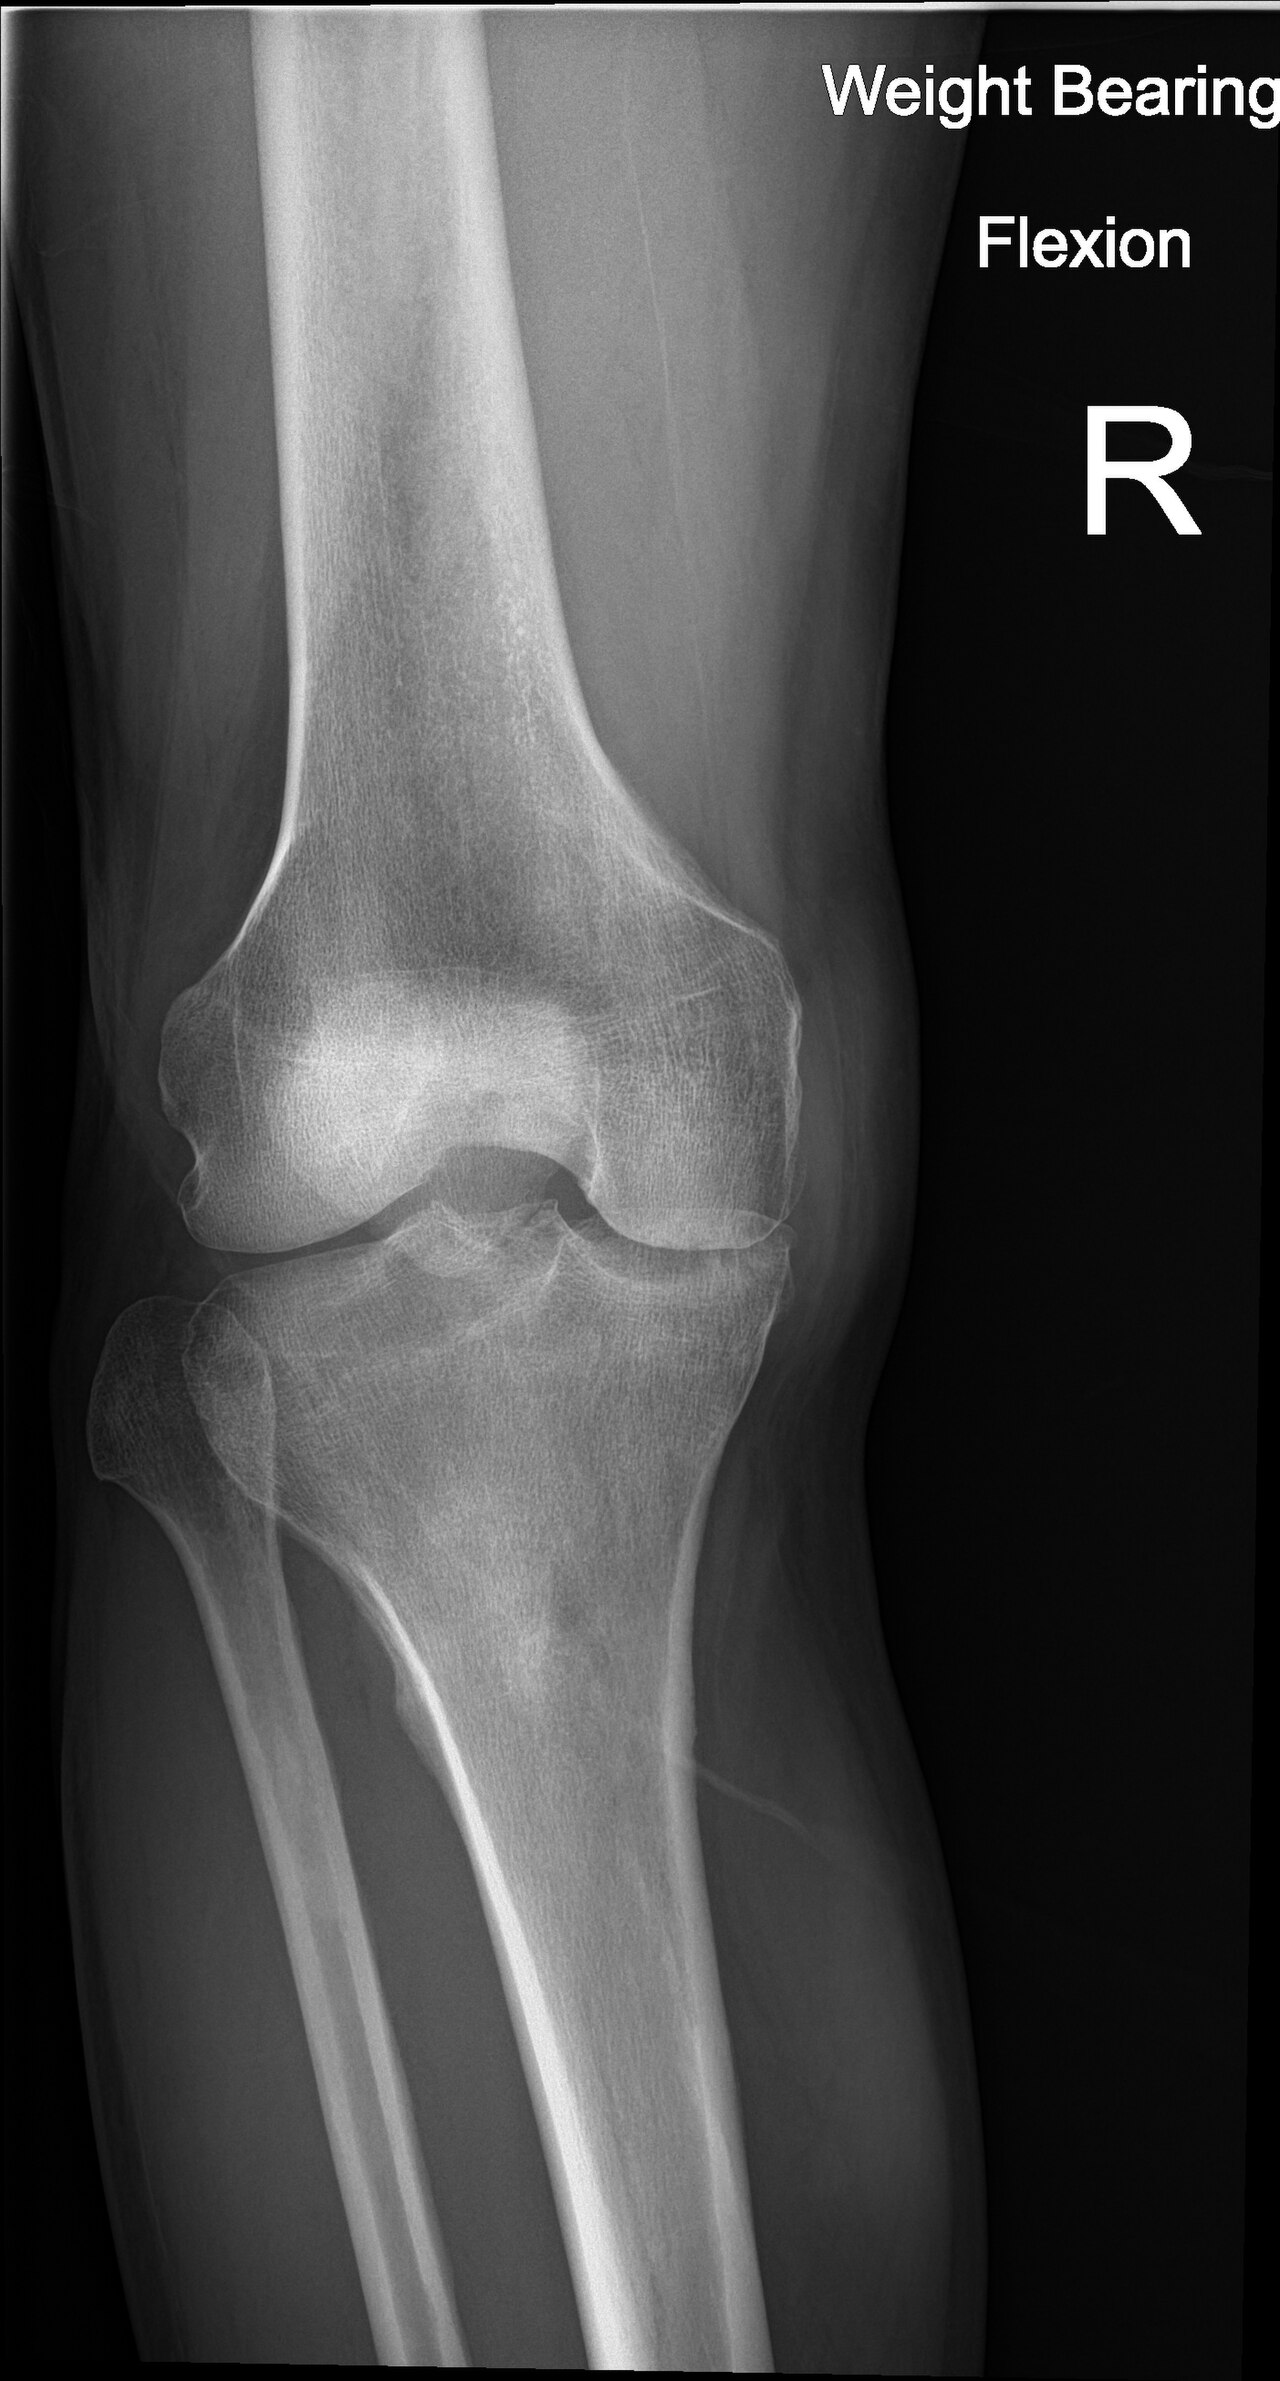

Normal knee phantom with intact bone, cartilage, menisci, and ligaments for baseline comparison

Degenerative knee with joint space narrowing, osteophytes, subchondral sclerosis, cartilage thinning, and Baker's cyst